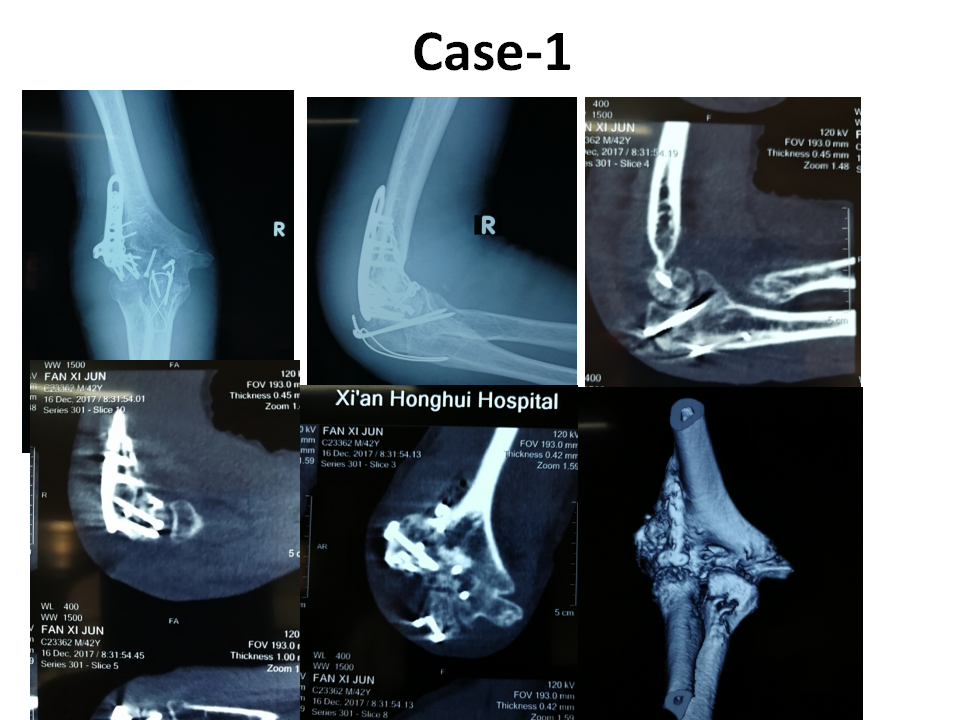

肱骨小头骨折病例分享